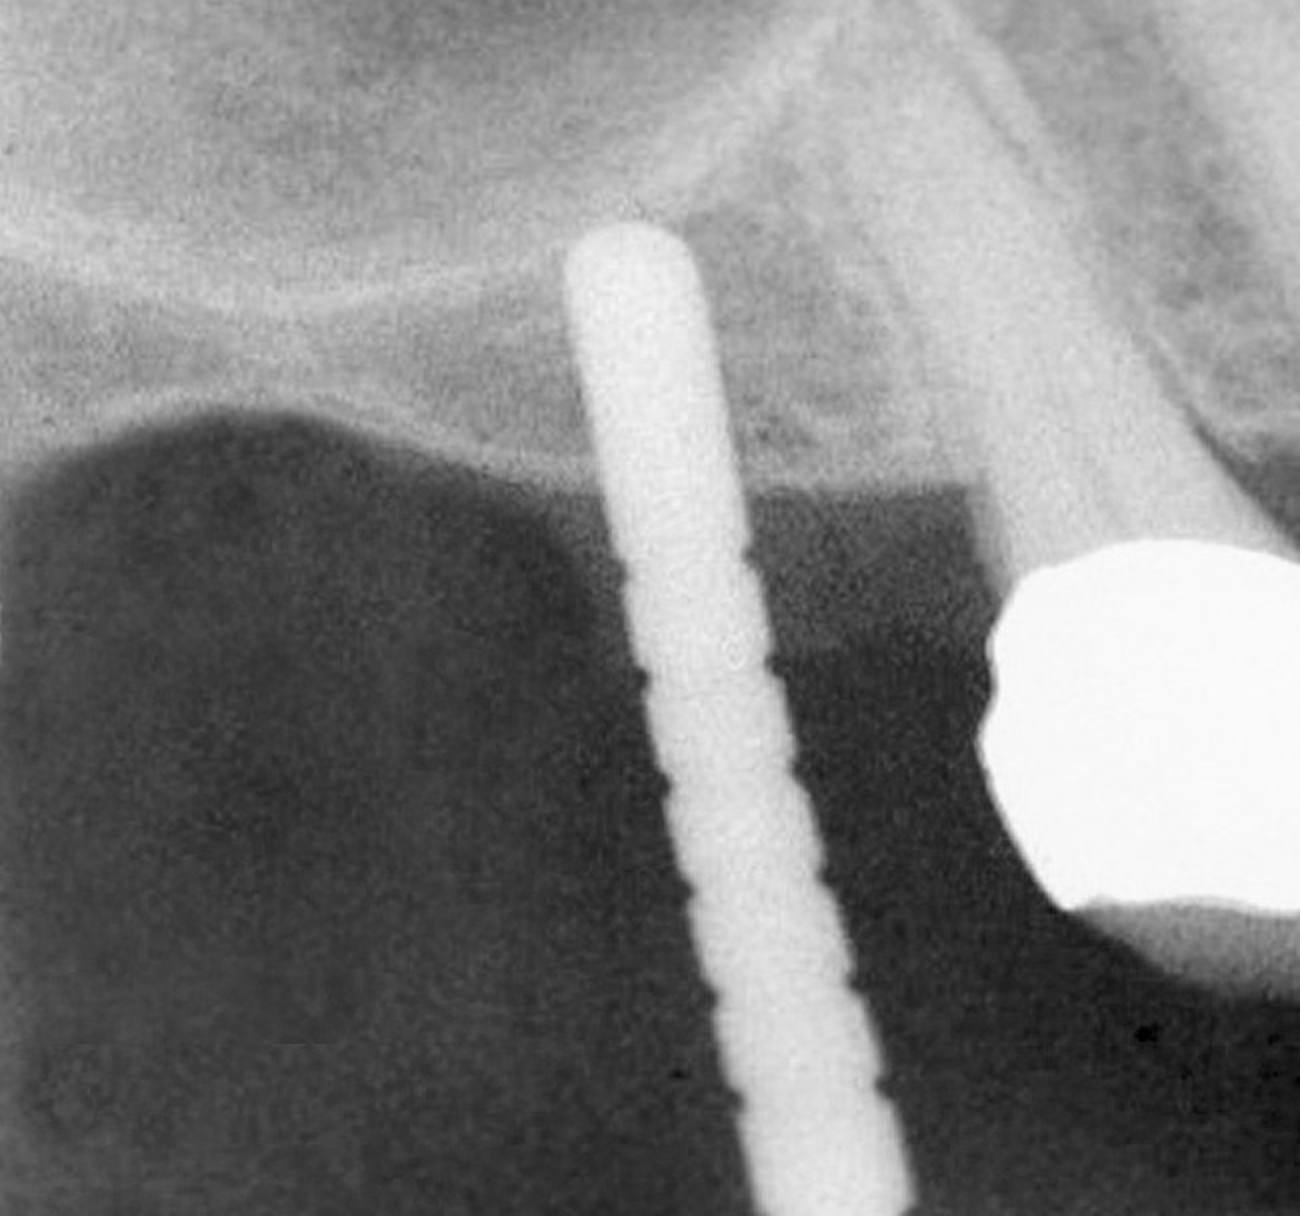

Figure 9: After the extraction, a 2.1-mm twist drill was used to drill within 1 mm of the subantral floor. A guide pin was placed and a radiograph was taken to ascertain if the drill stopped within 1 mm of the subantral floor.

Figure 9